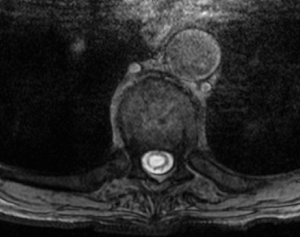

syrinx

Figure 1: T8-9 syrinx